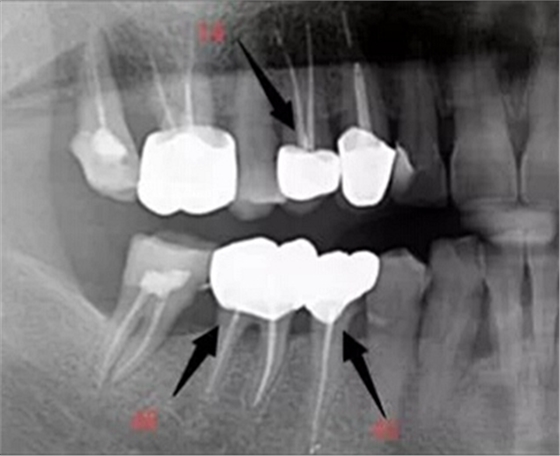

根管治療術(shù)又稱牙髓治療,是牙醫(yī)學(xué)中治療牙髓壞死和牙根感染的一種手術(shù)。該手術(shù)保留了牙齒,先是揭開髓室,頂敞開通路,用拔髓針拔除感染的牙髓。在用擴(kuò)挫針擴(kuò)凈根管壁,之后在根管內(nèi)封消炎藥,最后再用牙膠尖充填,手術(shù)繁瑣,一般要2-4次就診才能完成。隨著技術(shù)和材料的進(jìn)步,活髓牙一次性根管治療術(shù),也在臨床應(yīng)用。